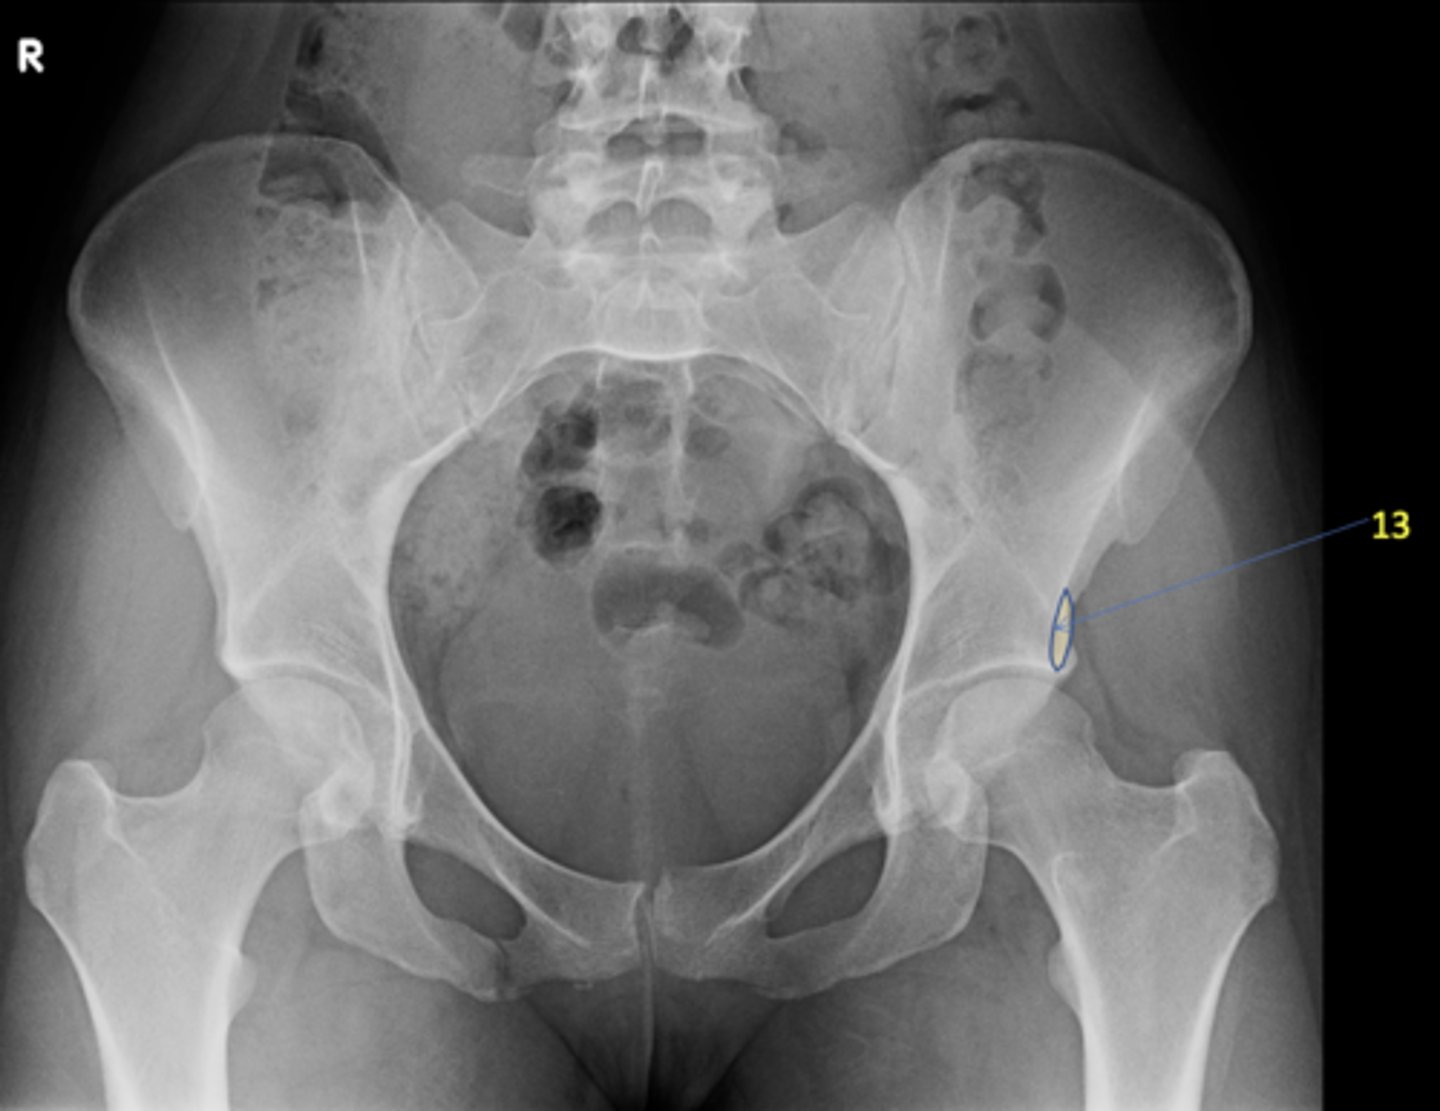

1

New cards

AP pelvis

View?

<p>View?</p>

13

Left anterior inferior iliac spine

ID 13

<p>ID 13</p>